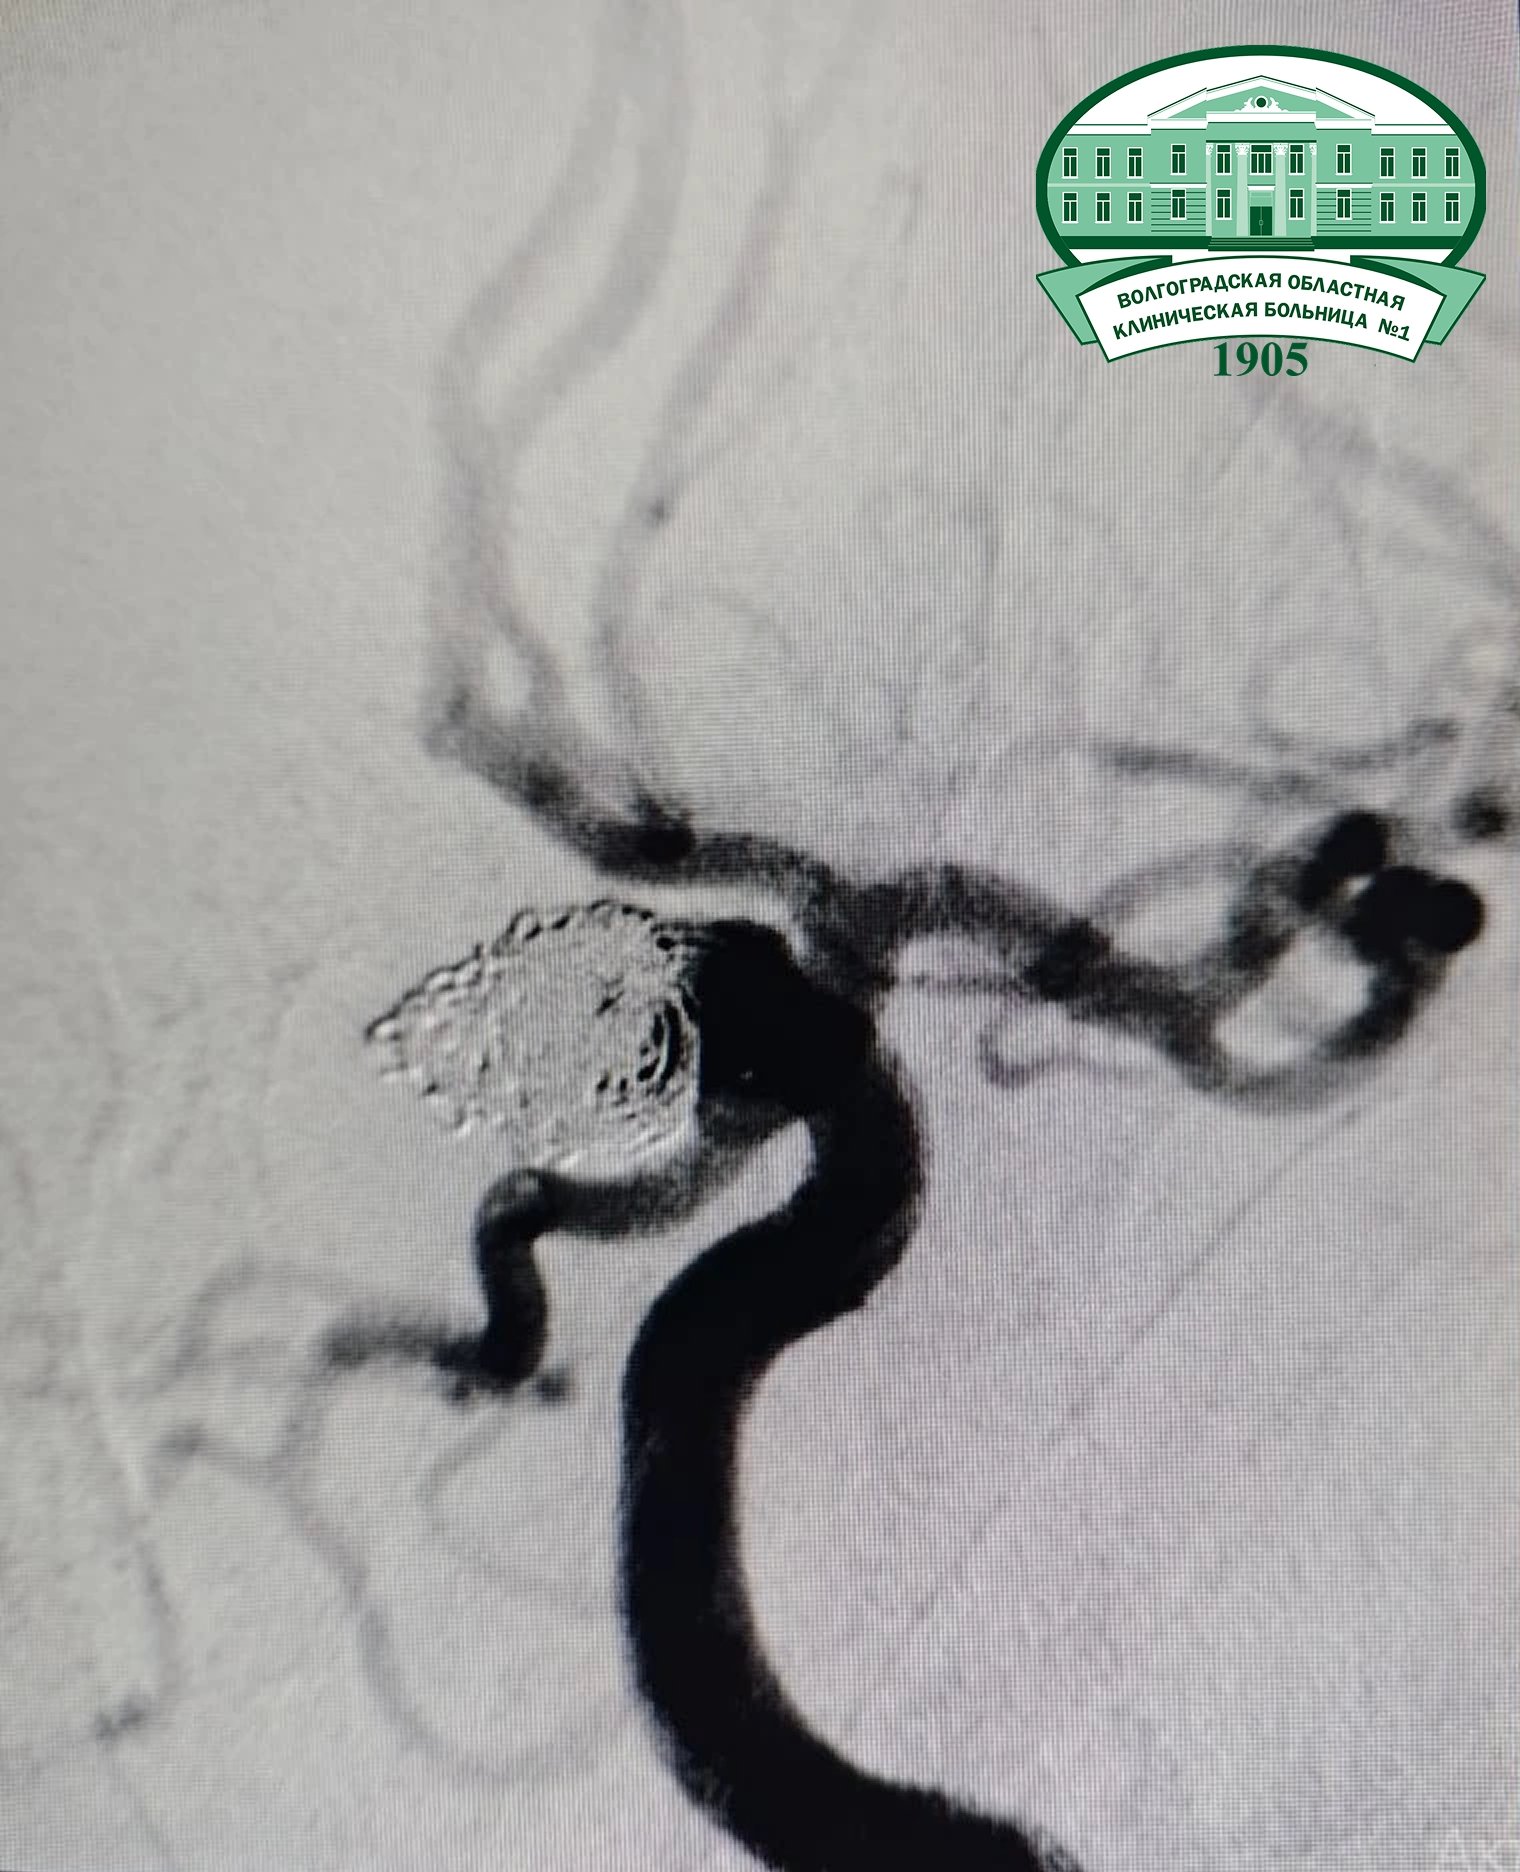

Ранним утром девушку обнаружили без сознания и срочно доставили в ВОКБ № 1. Компьютерная томография показала внутримозговое кровоизлияние.

Фото: Волгоградская областная клиническая больница № 1